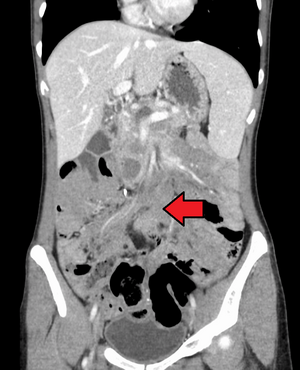

ورم رباطي كما هو موضح في الاشعة المقطعية | |

الورم الليفي العدواني هو حالة نادرة تتميز بوجود أورام خبيثة . تنشأ الأورام الخبيثة من خلايا تسمى الخلايا الليفية ، والتي توجد في جميع أنحاء الجسم وتوفر الدعم الهيكلي والحماية للأعضاء الحيوية ، وتلعب دورًا مهمًا في التئام الجروح. تميل هذه الأورام إلى الحدوث عند النساء في الثلاثينيات من العمر ، ولكن يمكن أن تحدث لأي شخص في أي عمر. يمكن أن تكون إما بطيئة النمو أو خبيثة. ومع ذلك ، فإن الورم الليفي العدواني عدواني محليًا ويمكن أن يسبب مشاكل تهدد الحياة أو حتى الموت عندما يضغط على الأعضاء الحيوية مثل الأمعاء والكلى والرئتين والأوعية الدموية والأعصاب. معظم الحالات متفرقة ، لكن بعضها يرتبط بداء السلائل الغدي العائلي (FAP). ما يقرب من 10 ٪ من الأفراد الذين يعانون من متلازمة جاردنر ، وهو نوع من FAP مع ميزات خارج القولون ، لديهم أورام رباطية .[1]